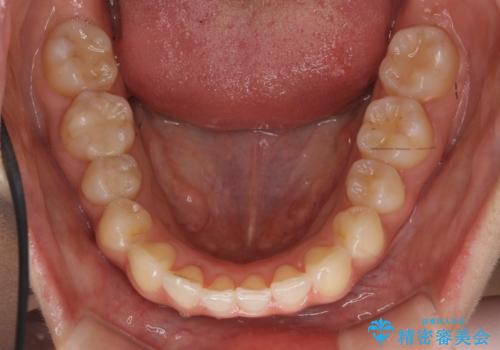

犬歯のねじれ 下の歯のがたがた インビザラインで

- 右上の犬歯のねじれ、下の歯のがたつきを主訴に来院。

インビザラインで歯を抜かずに並べました。

下の前歯のがたがたがそれなりにあったため、リファインメントを行いました。